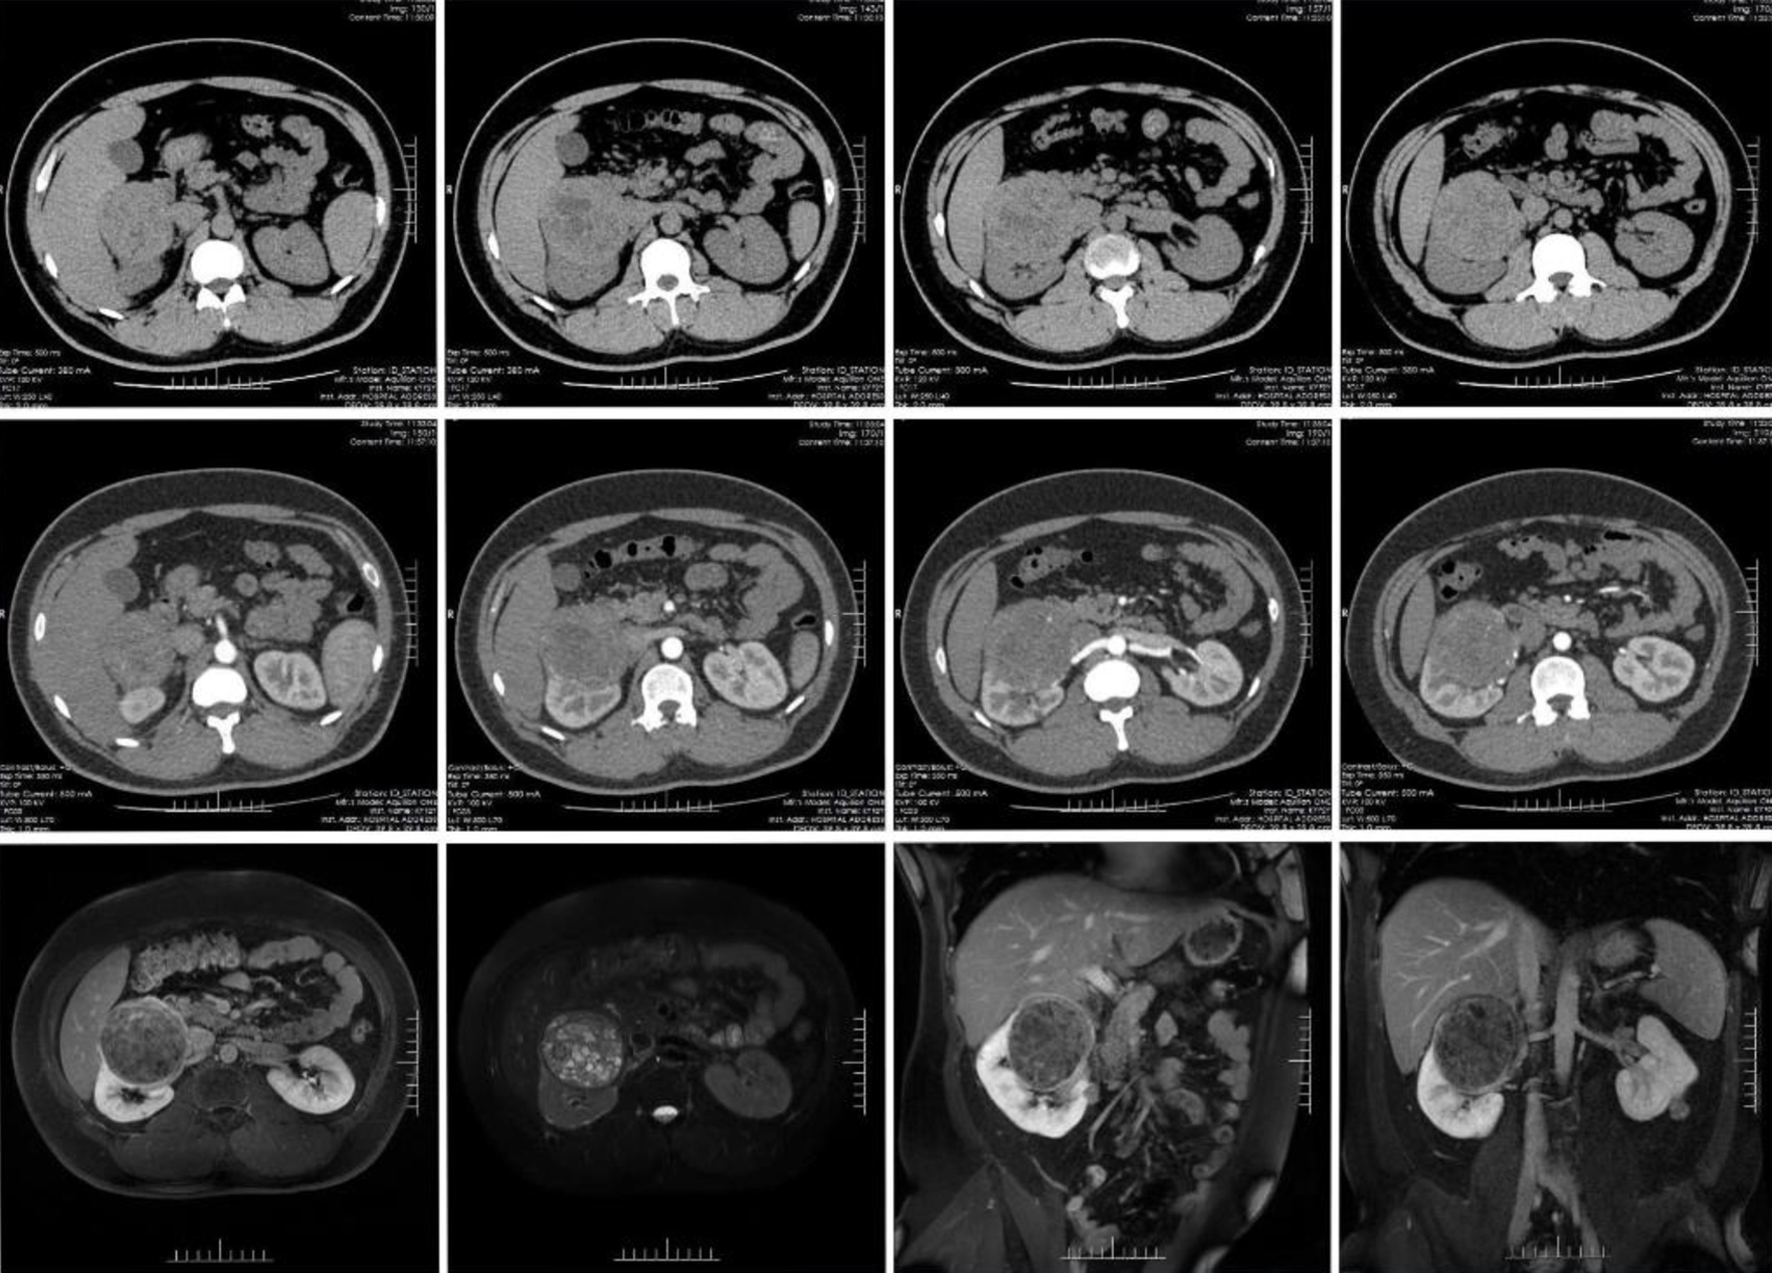

CT imaging of both kidneys displayed multiple nodular masses of medium and slightly high density, the largest located in the upper pole of the right kidney, measuring approximately 7.9 × 7.6 cm. The mass displaced surrounding tissues but maintained clear boundaries. The enhancement scan showed inhomogeneous enhancement of the mass, with an increased number of right renal artery branches and multiple small cystic shadows in the right renal pole. MRI revealed a mass at the upper pole of the right kidney, characterized by high T2-weighted image and mixed T1-weighted image signals. Diffusion-weighted imaging (DWI) and apparent diffusion coefficient (ADC) indicated mixed high and low signals. Mild, uneven enhancement was observed during both the parenchymal and excretory phases, with some boundaries being indistinct and compressing adjacent tissues. The small nodules in both kidneys exhibited high T2 and slightly elevated T1 signals, showing uneven enhancement following contrast administration. These findings raise the possibility of RCC or lipid-poor AML at the right kidney’s upper pole (Fig. 1). Routine blood tests, liver and kidney function assessments, electrolyte levels, coagulation profiles, renin-angiotensin system evaluations, and adrenocorticotropic hormone measurements were all within normal limits. The estimated glomerular filtration rate (eGFR) registered at 123 mL/min.

![]() Click for large image | Figure 1. The computed tomography (CT) and magnetic resonance imaging (MRI) of the patient. |